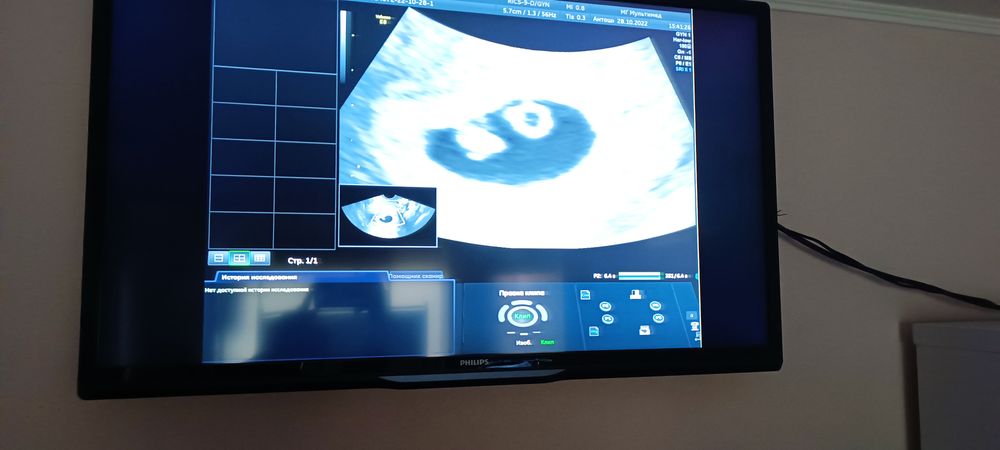

Девушки спасибо за поддержку ❤️. Врач УЗД .ничего особого и не сказала . Я пришла на контроль она узи делала 3 минуты .с.б прослушали есть. Измерила параметры эмбриона и желточного мешка.и всё. Я по изображению на маниторе вообще подумала двойня 🤣 а это эмбрион и ж. м. Решила прочесть информацию. И таких больших размеров как у меня никто и не пишет.